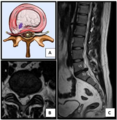

تحدث معظم حالات الانزلاق الغضروفي في العمود الفقري القطني (95% في الفقرات القطنية الرابعة-الخامسة أو الخامسة-العجزية الأولى).[21] الموقع الثاني الأكثر شيوعًا هو منطقة الفقرات العنقية (الخامسة-السادسة، السادسة-السابعة). تمثل منطقة الفقرات الصدرية 1-2% فقط من الحالات. تحدث الانزلاقات عادةً من الخلف إلى الجانب، عند النقاط التي تكون فيها الحلقة الليفية رقيقة نسبيًا ولا يتم تعزيزها بواسطة الرباط الطولي الخلفي أو الأمامي.[21] في العمود الفقري العنقي، يؤدي الانزلاق الخلفي الجانبي بين فقرتين إلى التأثير على العصب الذي يخرج من القناة الشوكية بين هاتين الفقرتين على هذا الجانب.[21] على سبيل المثال، فإن الانزلاق الخلفي الجانبي الأيمن للقرص بين الفقرتين العنقيتين الخامسة والسادسة سيؤثر على العصب الشوكي الأيمن للفقرة العنقية السادسة. ومع ذلك، فإن بقية الحبل الشوكي موجه بشكل مختلف، لذا فإن الانزلاق الخلفي الجانبي العرضي بين فقرتين سيؤثر على العصب الذي يخرج عند المستوى الفقري التالي إلى الأسفل.[21]

تحدث الانزلاقات الغضروفية القطنية في الظهر، وغالبًا ما تكون بين الفقرتين القطنيتين الرابعة والخامسة أو بين الفقرة الخامسة والعجز. وهنا يمكن الشعور بالأعراض في أسفل الظهر والأرداف والفخذ ومنطقة الشرج/الأعضاء التناسلية (عبر العصب العجاني)، وقد تنتشر إلى القدم و/أو إصبع القدم. العصب الوركي هو العصب الأكثر تأثرًا، مما يسبب أعراض عرق النسا. يمكن أن يتأثر العصب الفخذي أيضًا ويسبب للمريض شعورًا بالخدر والوخز في جميع أنحاء إحدى الساقين أو كلتيهما وحتى القدمين أو شعورًا بالحرقان في الوركين والساقين.[22] غالبًا ما يضغط الانزلاق في منطقة أسفل الظهر على جذر العصب الذي يخرج من المستوى أسفل القرص. وبالتالي، فإن فتق الفقرة القطنية الرابعة والخامسة يضغط على جذر العصب القطني الخامس، فقط إذا كان الانزلاق خلفيًا جانبيًا.[بحاجة لمصدر]

رسم توضيحي يصور الانزلاق الغضروفي وضغط العصب الفقري.

انزلاق غضروفي خلال تمزق في الحلقة (موضح بالتصوير بالرنين المغناطيسي).[9]